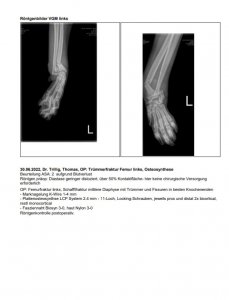

16.07.2022 Casi's Unfall… und nun auch noch Cosimo verletzt Beitrag #206 mennemaus Ehren-Mitglied Beiträge 24.139 Reaktionspunkte 17.737 Au wei, wenn man diese Fotos sieht, weiß man erst, wie schlimm die Verletzungen von Casi gewesen sind. Toll, dass die Ärzte es geschafft haben, die zerbröselten Knochen wieder zusammenzusetzen. Dein Casi hat richtig Glück gehabt, dass die Ärzte nicht amputiert haben, sondern dass sie die schwierige OP gewagt haben. Hoffentlich heilt das alles gut und hoffentlich bleiben keine Folgeschäden von dem Unfall übrig. Alles Gute für den kleinen Racker.

16.07.2022 Casi's Unfall… und nun auch noch Cosimo verletzt Beitrag #211 Fusselschreck Beiträge 1.755 Reaktionspunkte 981 @Dextro Das habe ich mich auch gefragt, habe das erst zu Hause gesehen. Nächste Woche ist Kontrollröntgen, Mal sehen wie es dann aussieht. Da kann ich dann Mal nachfragen.

@Dextro Das habe ich mich auch gefragt, habe das erst zu Hause gesehen. Nächste Woche ist Kontrollröntgen, Mal sehen wie es dann aussieht. Da kann ich dann Mal nachfragen.

16.07.2022 Casi's Unfall… und nun auch noch Cosimo verletzt Beitrag #215 Rena 44 Beiträge 974 Reaktionspunkte 683 Ich bin auch total geschockt von diesen Bildern , unglaublich wie die Ärzte dieses Beinchen wieder hinbekommen , das das länger dauert bis alles wieder belastbar ist ist klar .. aber daß es überhaupt möglich war ist fantastisch

Ich bin auch total geschockt von diesen Bildern , unglaublich wie die Ärzte dieses Beinchen wieder hinbekommen , das das länger dauert bis alles wieder belastbar ist ist klar .. aber daß es überhaupt möglich war ist fantastisch

16.07.2022 Casi's Unfall… und nun auch noch Cosimo verletzt Beitrag #220 Stefanie- Beiträge 13.756 Reaktionspunkte 12.355 Wenn man die Röntgenbilder sieht wird's einem ganz übel, toll wie die Ärzte das hingekriegt haben! Alles Liebe und gute Besserung für den Süßen.

Wenn man die Röntgenbilder sieht wird's einem ganz übel, toll wie die Ärzte das hingekriegt haben! Alles Liebe und gute Besserung für den Süßen.